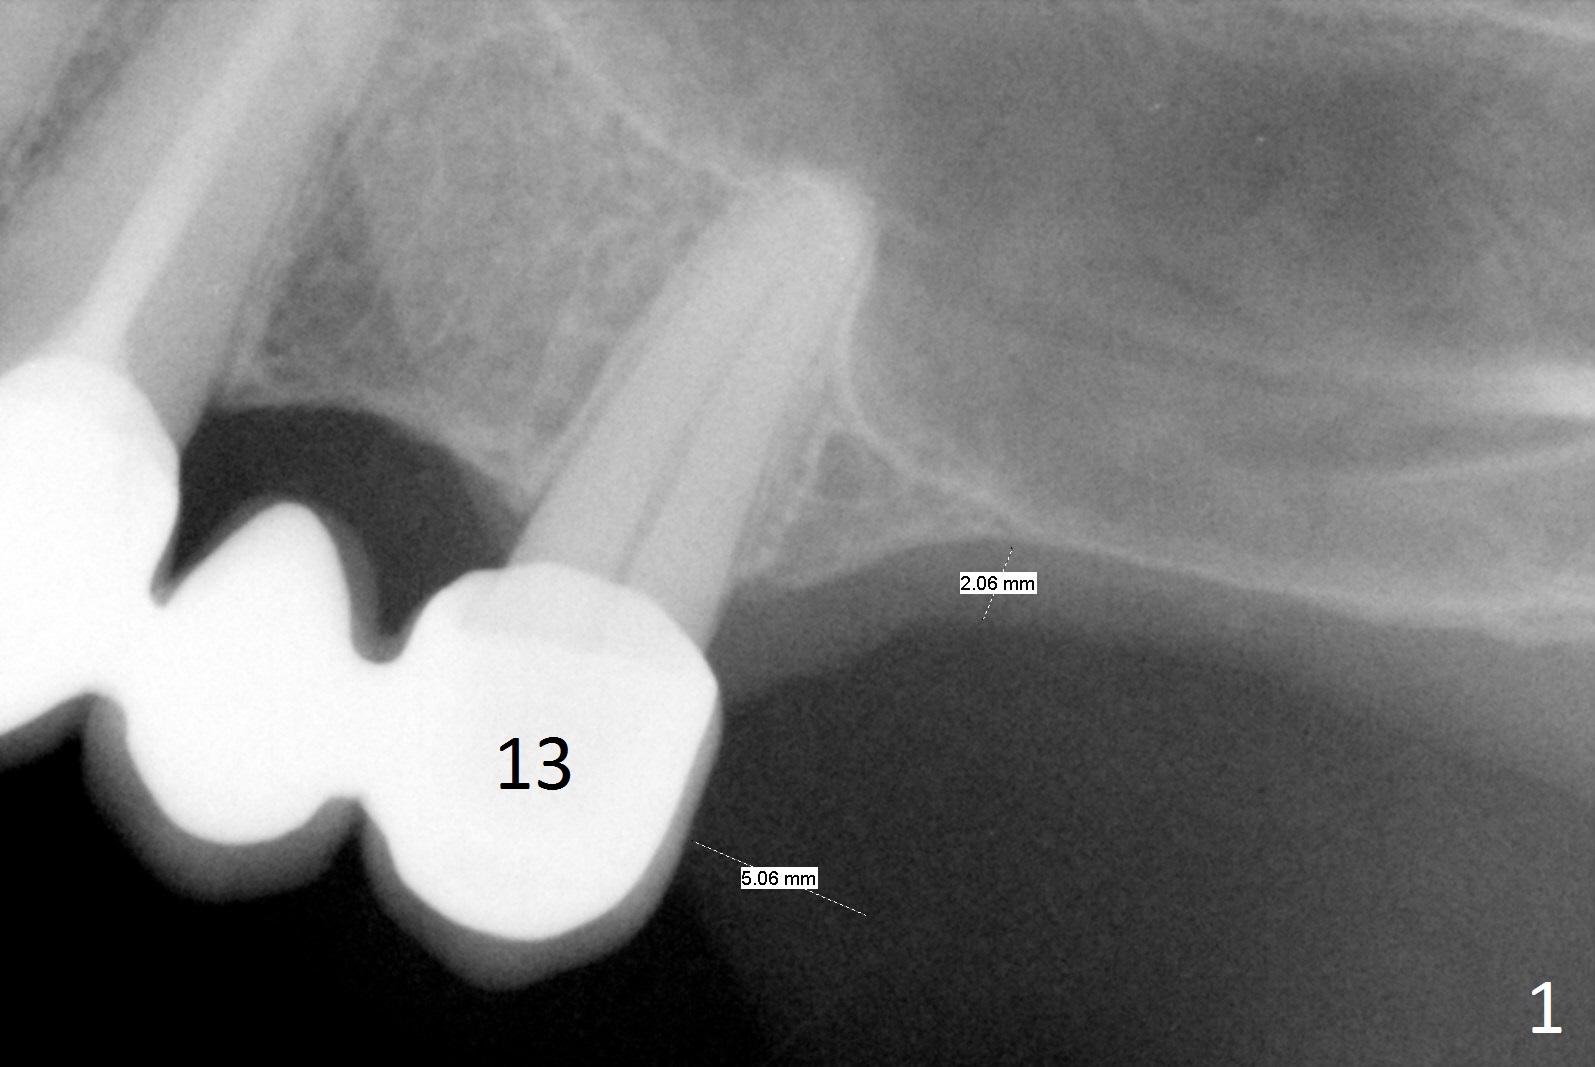

A 52-year-old woman is a dental phobic. Finally she agrees to have 1 implant placed in the upper left posterior region, where the sinus floor is paper thin (Fig.1). Use Magic Split for access for 2-3 mm deep, followed by Magic Lifter for 9 mm. If the latter does not engage, use Magic Drill in the Sinus Kit. Place PRF membranes (Fig.2,3 purple curved line) and allograft/Osteogen (circles) prior to 4 mm dummy implant. The 1st intraop PA will show whether the graft is sufficient or not. Since the mesial bone is thicker than the distal one (Fig.1,2), try to prevent the osteotomy from drifting distally (1).